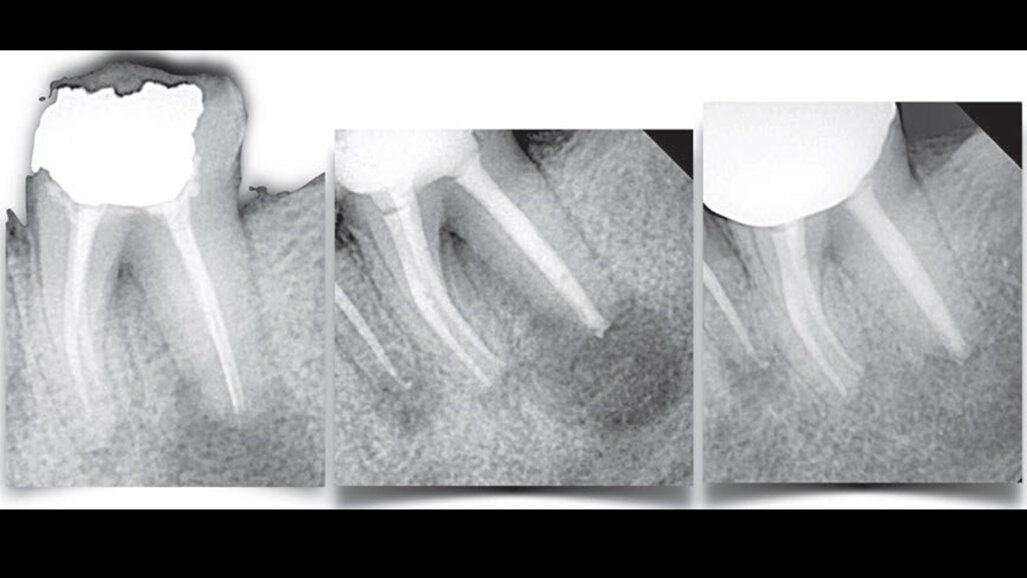

Il trattamento e la prevenzione della parodontite periapicale a seguito di trattamenti falliti sono notevolmente più complessi rispetto ai trattamenti primari. Nei trattamenti primari, il sistema dei canali radicolari, nonostante la sua complessità, può essere gestito efficacemente con gli attuali protocolli di sagomatura e pulizia, raggiungendo percentuali di successo del 95% nella maggior parte dei casi. Tuttavia, nei casi in cui l'insuccesso del trattamento rende necessario il ritrattamento, ulteriori fattori o sfide possono complicare la situazione. Questi includono la rimozione di precedenti materiali di otturazione radicolare, l'anatomia alterata, la presenza di perforazioni, l'ostruzione canalare (iatrogena o biologica), il riassorbimento infiammatorio e l'incapacità di raggiungere la pervietà attraverso il forame, che è fondamentale. Inoltre, la presenza di una lesione apicale si aggiunge a queste complicazioni. Tali difficoltà, combinate con la natura intrinsecamente complessa del sistema dei canali radicolari, rendono i ritrattamenti significativamente più impegnativi rispetto ai trattamenti primari e spesso si traducono in tassi di successo inferiori.

Il recupero dell'accesso al sistema dei canali radicolari può essere impegnativo, soprattutto quando sono stati utilizzati perni in fibra come elementi di ritenzione intracanalare. I medici devono avere l'esperienza necessaria e gli strumenti adeguati per evitare errori iatrogeni. Per quanto riguarda i materiali da otturazione intracanalare, è necessario un approccio diverso ma dinamico. Esistono infatti diversi tipi di materiali da otturazione radicolare, tra cui i vecchi punti d'argento, la guttaperca e i materiali in silicato di calcio, ampiamente utilizzati, ognuno dei quali richiede un metodo di rimozione distinto per recuperare il pieno accesso al sistema dei canali radicolari. Una rimozione inadeguata di questi materiali durante i ritrattamenti può compromettere il risultato del trattamento. I residui possono limitare l'accessibilità dei disinfettanti e degli strumenti alle microanatomie o possono causare un sigillo inadeguato.

L’endodonzia è una specialità molto dinamica e in rapida evoluzione. Ha beneficiato dei progressi delle modalità di imaging, come la CBCT, che consente una visualizzazione precisa dei problemi dentali. I recenti progressi negli strumenti in nichel-titanio e nella loro cinematica, insieme all’introduzione di nuovi strumenti e dispositivi per la somministrazione e l’attivazione dell’irrigante, hanno contribuito a migliorare i risultati del trattamento. L’integrazione dell’ingrandimento e degli ultrasuoni nella pratica endodontica è un aspetto critico che ha trasformato in modo significativo la specialità. Queste tecnologie sono state fondamentali per varie procedure e persino per correggere precedenti errori. Inoltre, vorrei sottolineare la rapida evoluzione dei biomateriali endodontici, in particolare dei materiali a base di silicato di calcio. Questi si sono dimostrati utili nei ritrattamenti complessi, soprattutto nei casi che coinvolgono difetti radicolari o anatomie difficili. Inoltre, ci sono stati progressi significativi nei concetti e nei materiali per la fase restaurativa post-endodontica, che giocano un ruolo cruciale nell’estendere il tempo di sopravvivenza dei denti trattati.